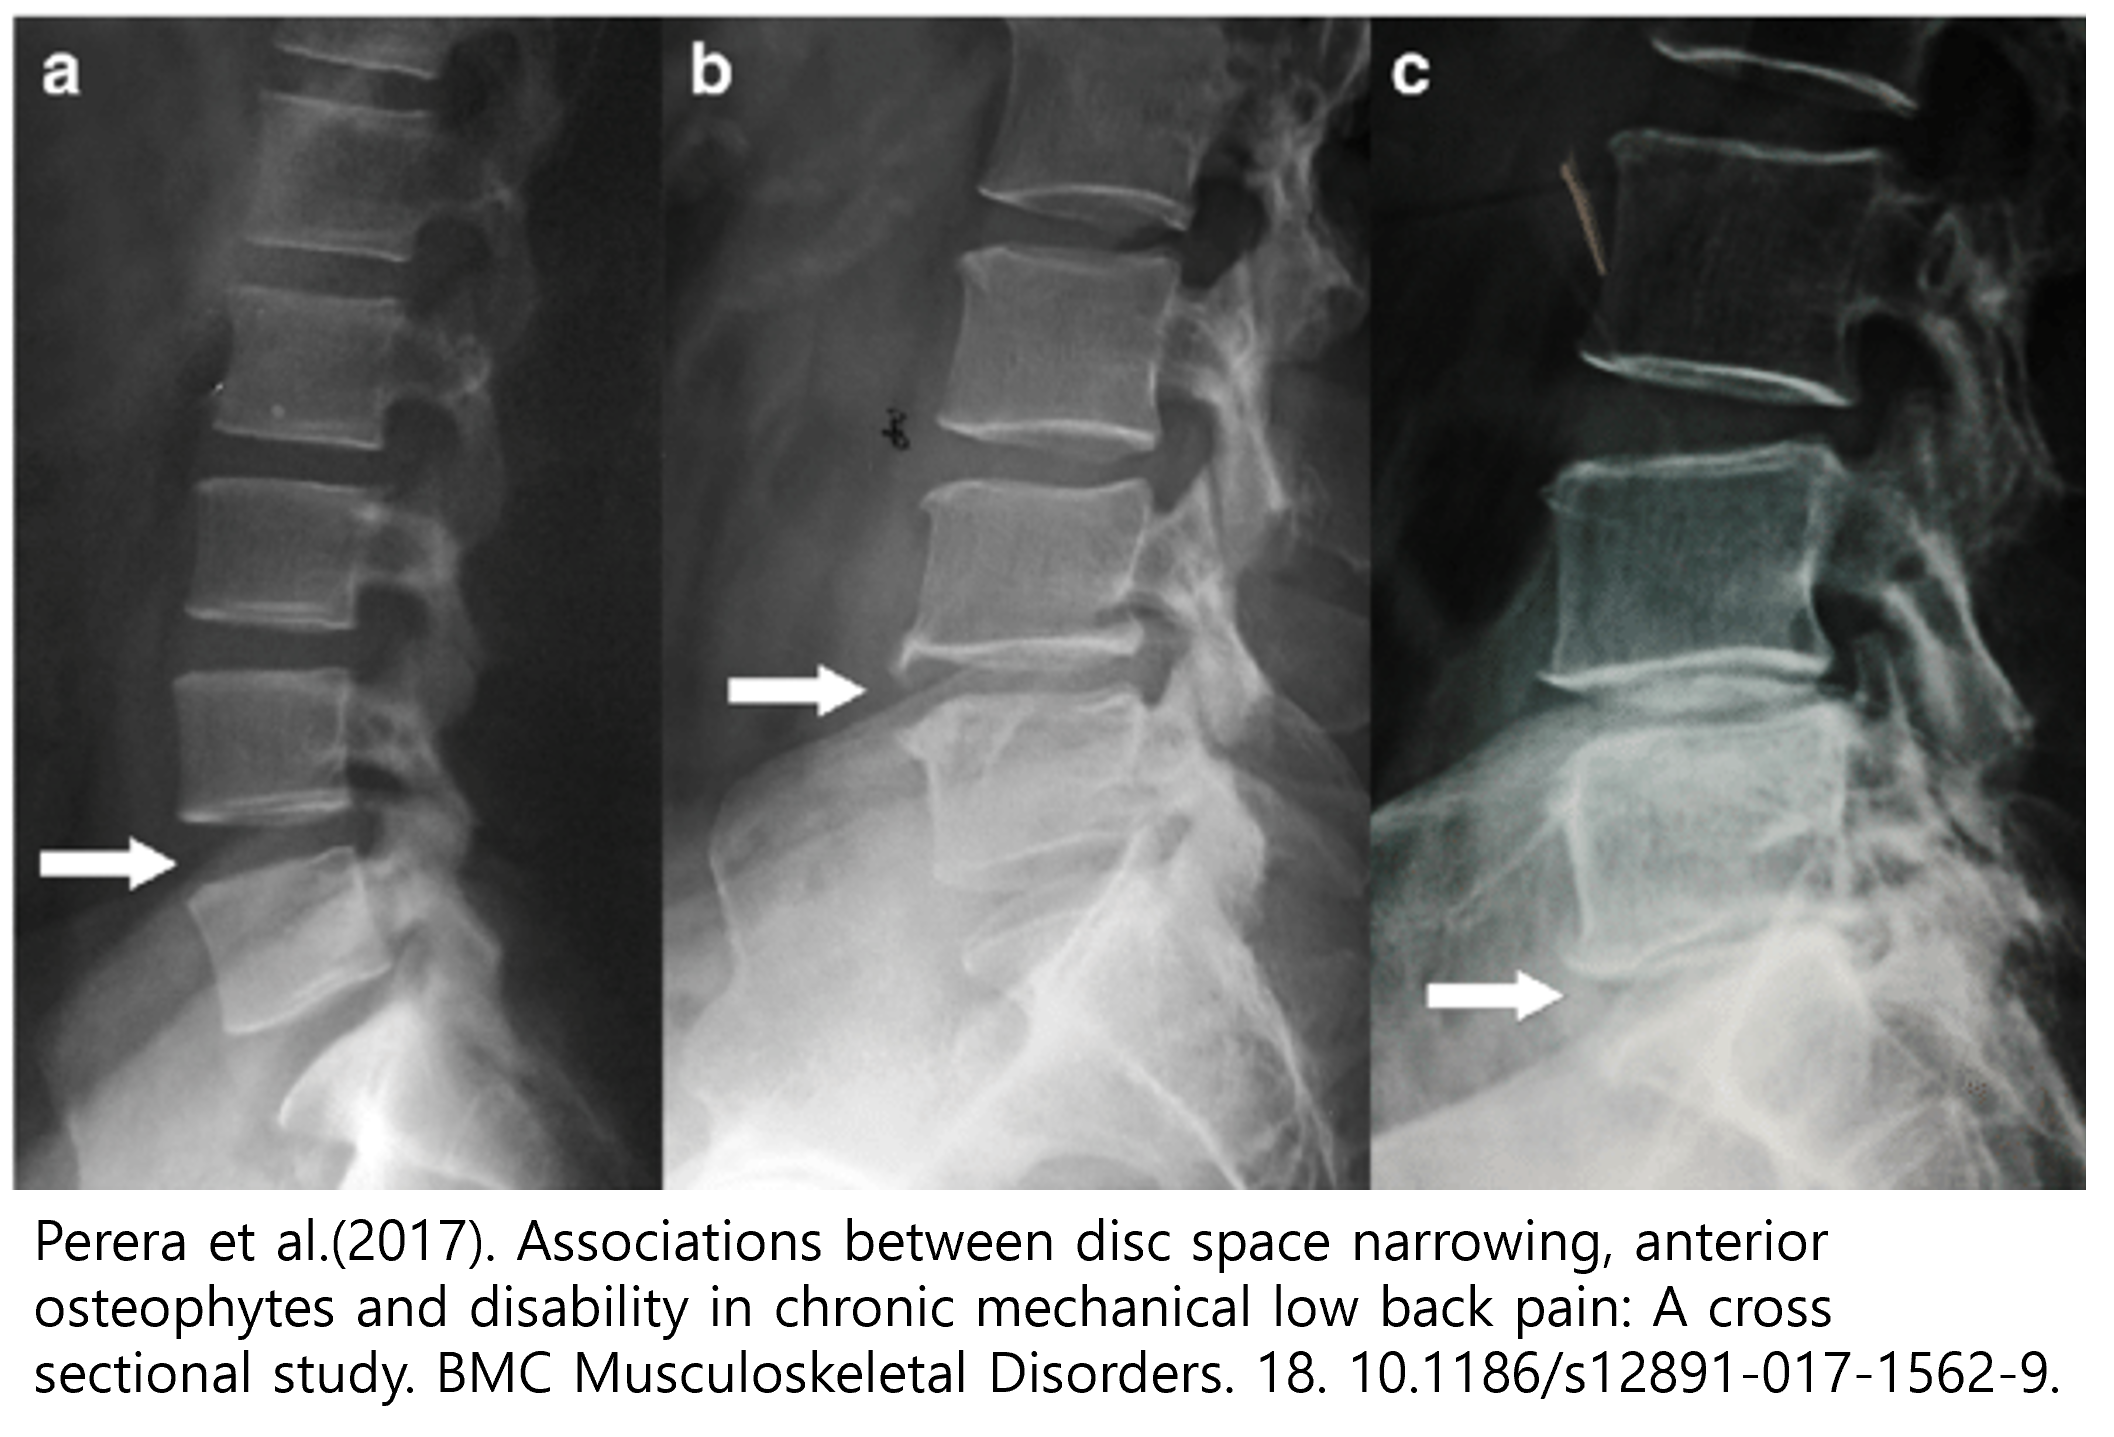

이러한 소견은 염좌에 관한 간접적인 소견에 해당하는데요, 그렇다면 좀 더 심각한 질병을 감별할 수 있는 소견은 무엇일까요? 디스크는 맨 처음 모식도 그림에서 보신 것처럼 척추 뼈 사이사이를 메꾸고 있는 콜라겐 조직입니다. 디스크의 손상은 결국 이러한 콜라겐 조직의 퇴행성 변화를 야기하게 되고, 그 결과 만성 디스크 환자의 경우 손상된 디스크의 높이가, 정상적인 디스크의 높이보다 낮아지게 됩니다.

또한 디스크의 기능 중 하나인 '관절의 안정성'이 무너지기 때문에, 망가진 디스크와 인접한 두 척추 뼈가 불안정하게 흔들리게되고, 이를 보상하기 위해 뼈가 자라나며 두 뼈 사이를 이어주려고 하는, 골극 형성이 일어나는 것도 확인 할 수 있습니다.